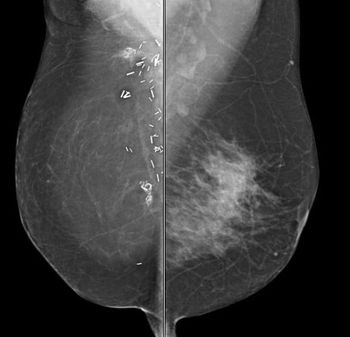

A 54-year-old patient presented for evaluation of spontaneous left breast discharge. The patient is status post-right mastectomy with TRAM reconstruction in 1999. The patient states she has noted left breast discharge for quite some time.